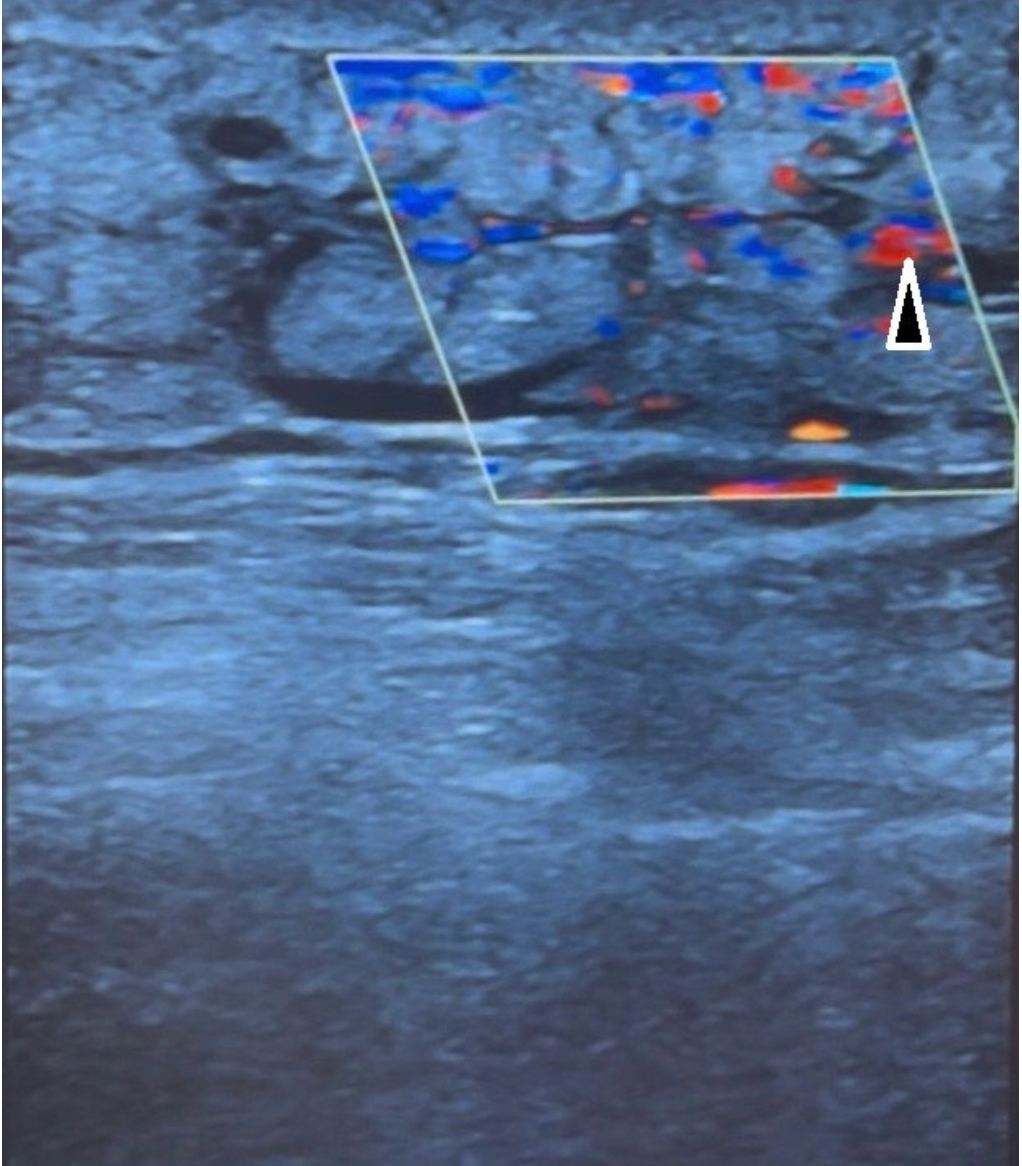

Color Doppler showed increased vascularization of the subcutaneous tissue, which supports an inflammatory etiology.

Figure 4. Color Doppler showed increased vascularization of the subcutaneous tissue, which further supports the inflammatory etiology